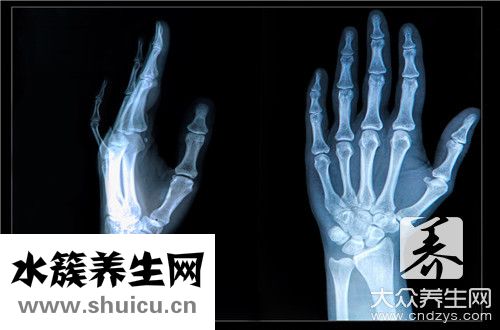

生活中會(huì)發(fā)現(xiàn)一個(gè)問題。 那是有人骨折后不知道,最后完全腫脹后才知道自己是骨折。 特別是手指這樣的部位摸起來很痛,但是會(huì)瞬間麻木,所以不會(huì)被認(rèn)為是骨折。 逐漸腫脹之后,才能知道里面發(fā)生了什么。...